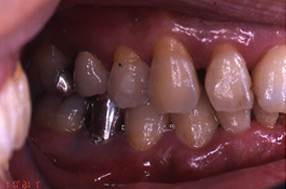

■歯周病治療例

歯周病の進行に伴う歯肉の

炎症と歯の移動が見られます。

歯周外科手術と同時に矯正で

歯周組織の再生と審美回復と

なりました。